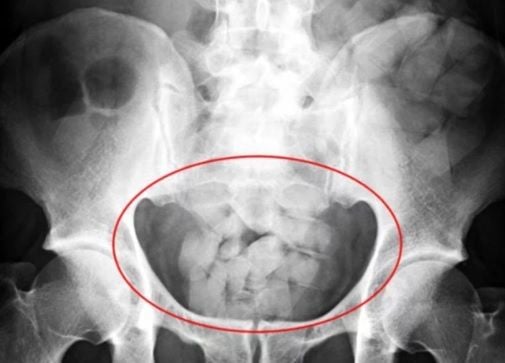

Dos ciudadanos de nacionalidad boliviana fueron detenidos ayer en la Terminal de Omnibus, acusados de transportar drogas en el interior de su cuerpo.

Tras ser llevados al Hospital, uno de ellos arrojó casi un kilo de cocaína que había ingerido y tenía en su estómago; mientras que el otro expulsó medio kilo. Este último se encuentra en grave estado de salud.